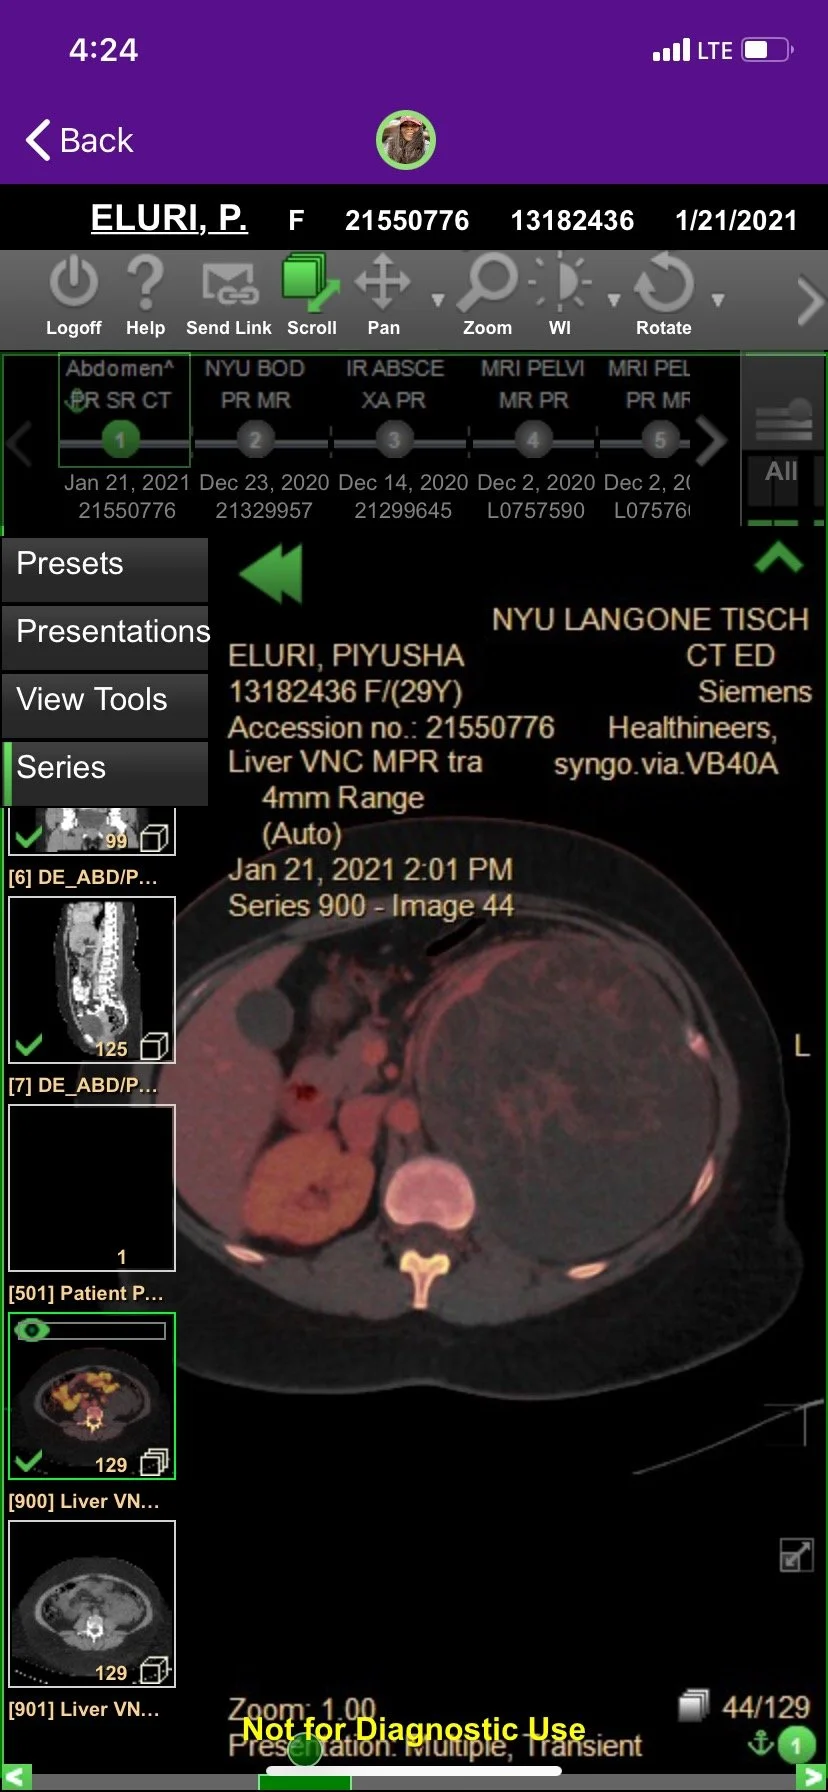

Jan 2021

Left Radical Nephrectomy Of 20cm Mass

After 1.5 months of at home care and an uncertain diagnosis, Piyusha was rushed into emergency surgery on January 22, 2021 which was successful with margins.